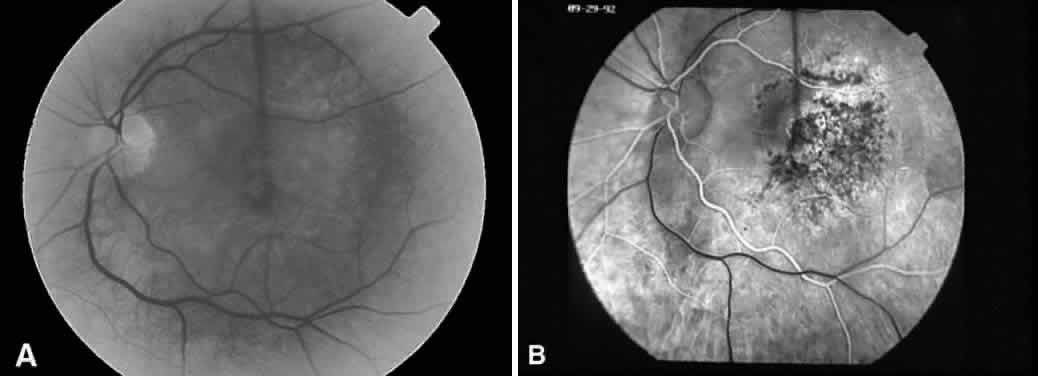

Recognizing light toxicity in the posterior segment may be difficult and is under reported because the findings can be extremely subtle on examination and many cases are asymptomatic. However, clinical features of such lesions are now well described, and when they occur in a high-risk situation, a diagnosis usually can be made. An accompanying fluorescein angiogram (Fig. 2) or visual field test can support a diagnosis if clinical suspicion is high.

Fig. 2. A. Fluorescein angiography of a 49-year-old patient with a malignant melanoma on the left iris who consented to deliberate induction of photic retinopathy by the operating microscope before scheduled enucleation of that eye. Red-free photograph of the normal posterior pole of the left eye pre-exposure. B. Late phase of the angiogram, pre-exposure, demonstrates a normal macula. C. Red-free photograph of the left eye after light exposure showing a vertically oriented lesion centered in the macula. D. Late phase of the angiogram demonstrates hyperfluorescence in the area of photic damage. (Green WR, Robertson DM: Pathologic findings of photic retinopathy in the human eye. Am J Ophthalmol 112:520, 1991)